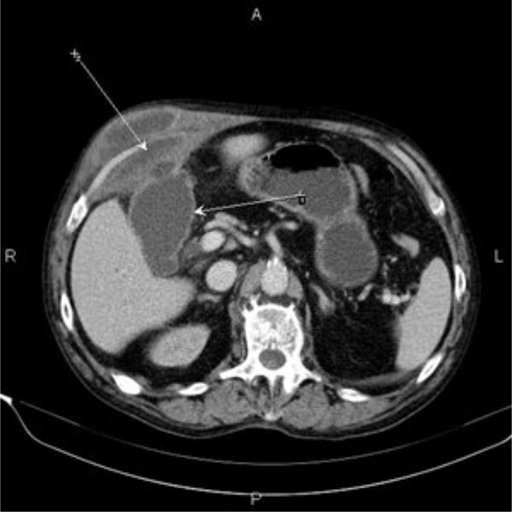

При госпіталізації, зважаючи на суперечливі дані ультразвукової діагностики, 20.01.2017 р. проведено комп’ютерну томографію

Встановлено діагноз гострого деструктивного холециститу з пенетрацією дна жовчного міхура в передню черевну стінку, утворенням фістули та розвитком субапоневротичного міжм’язового абсцесу з анаеробним компонентом. Окрім того, у хворого виявлено холедохолітіаз і механічну жовтяницю (білірубін - 98 ммоль/л).